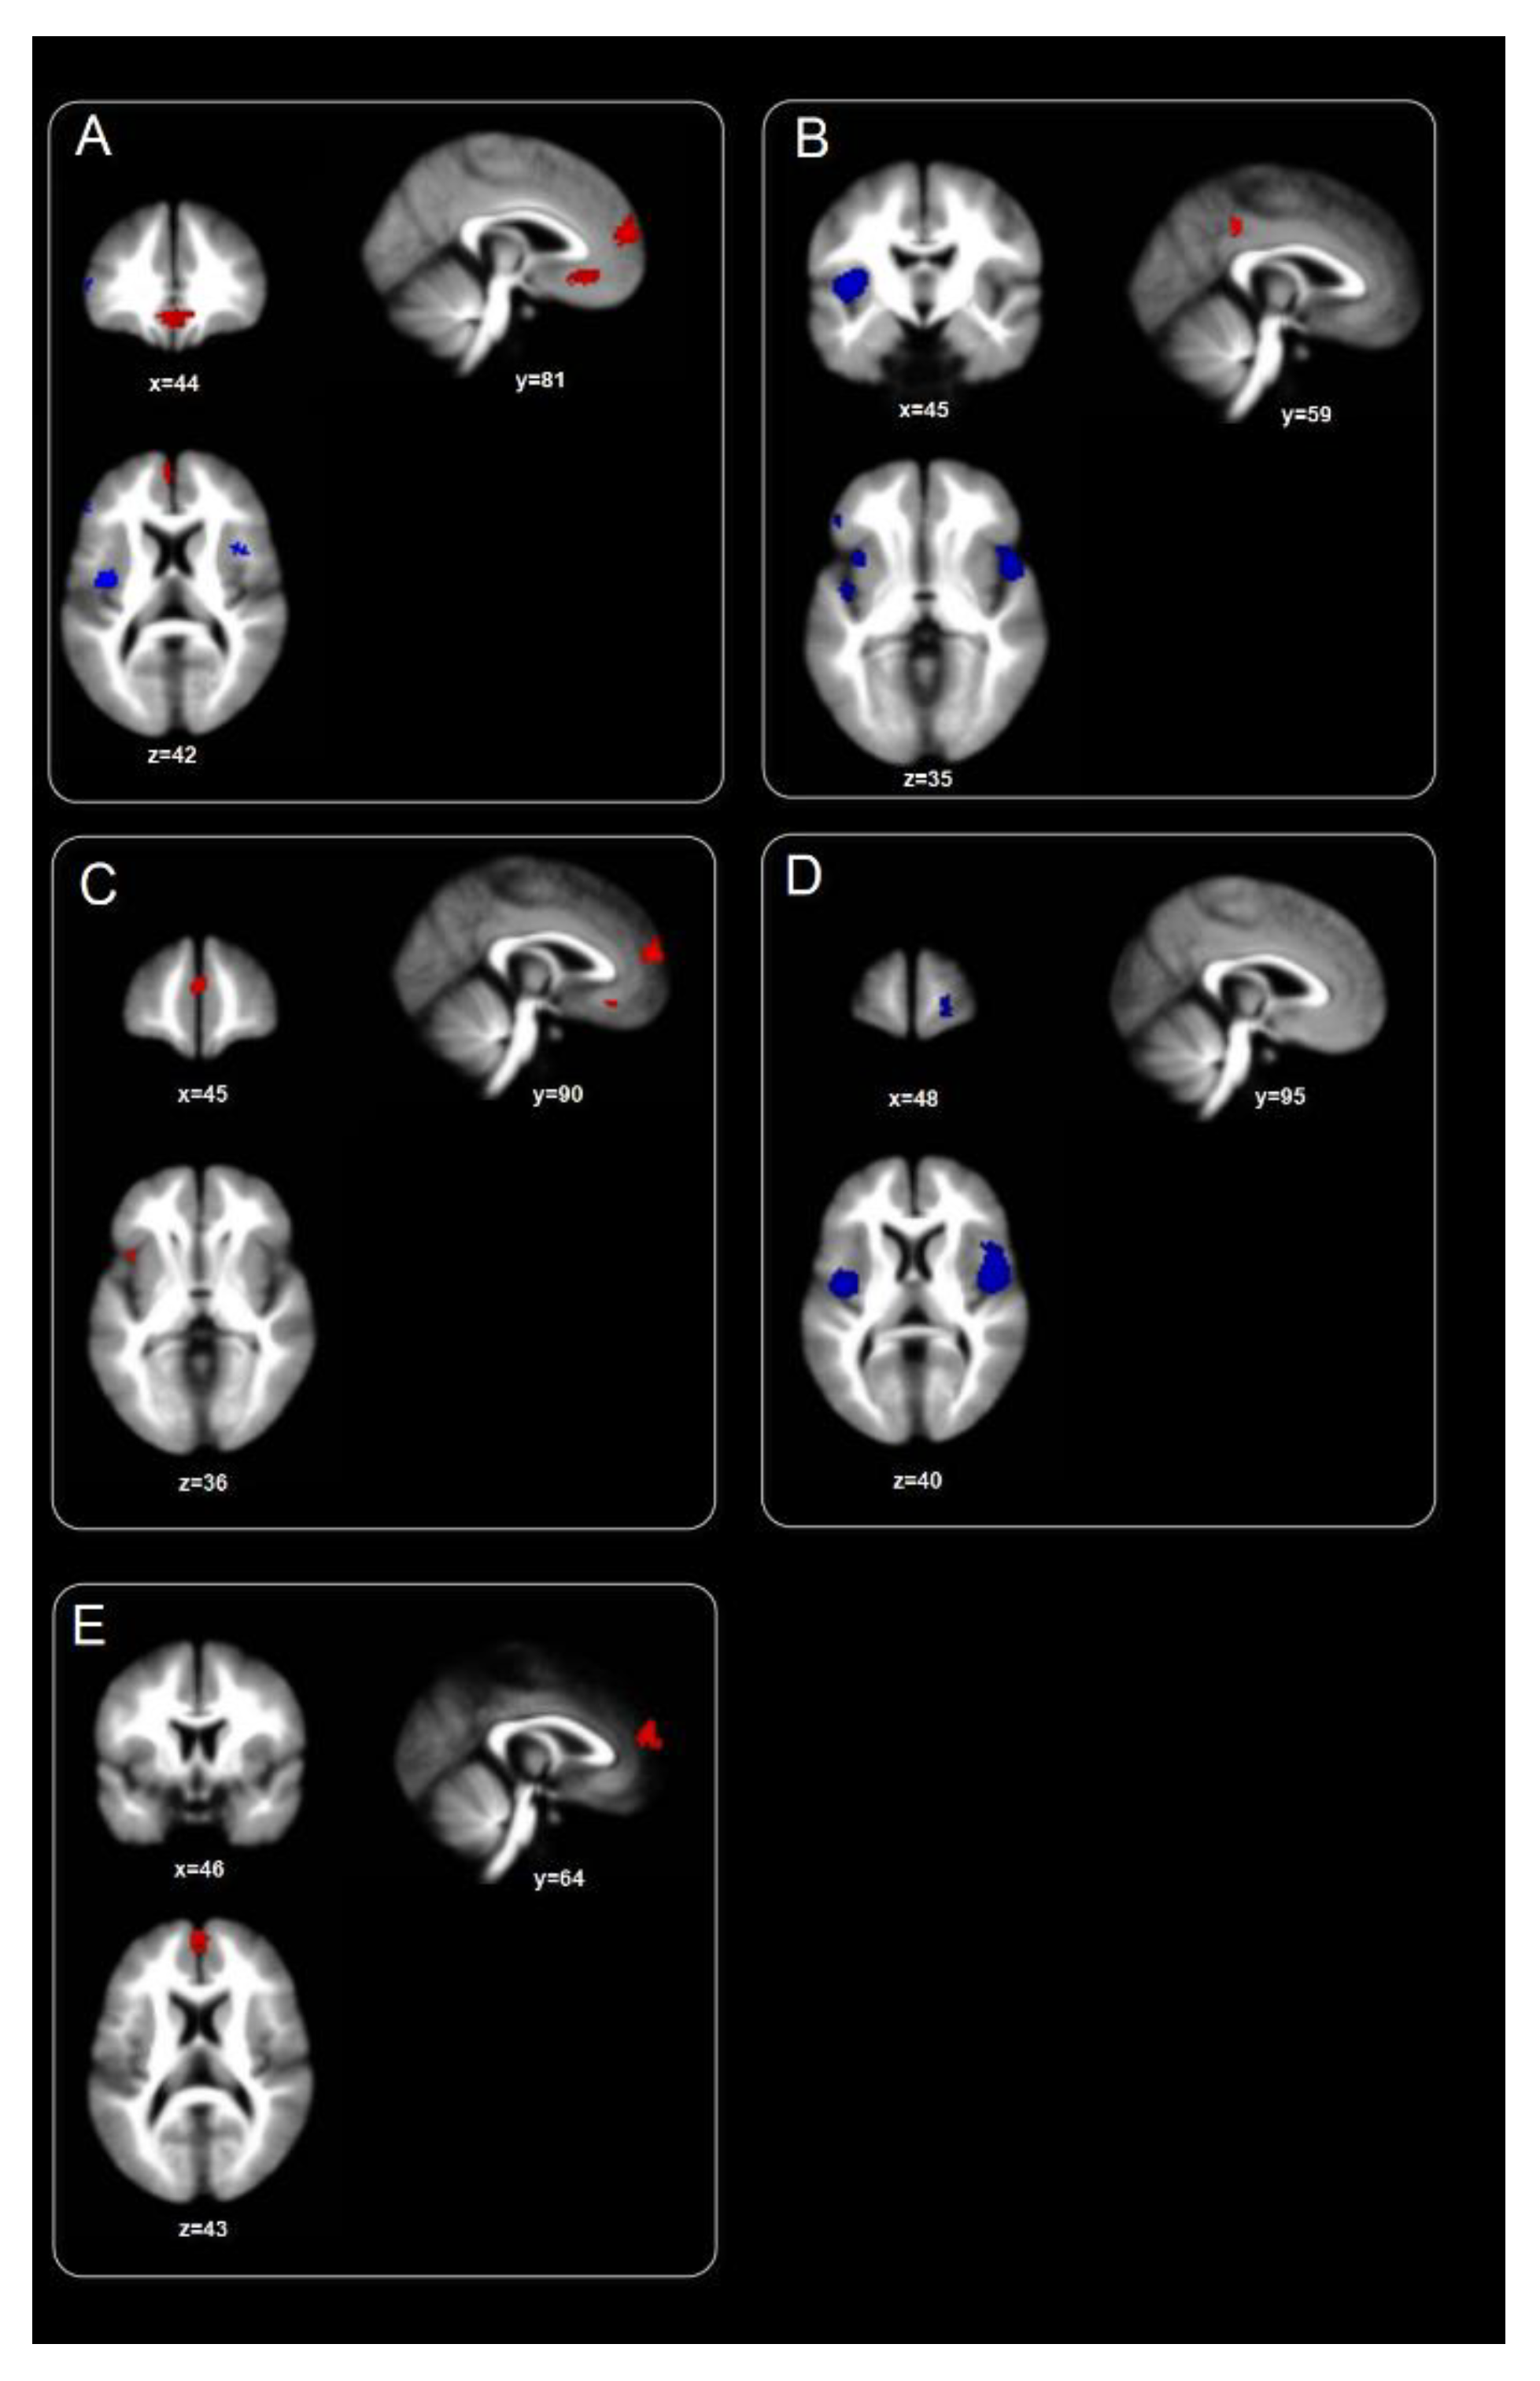

| Cluster | Hemisphere | Coordinates (X, Y, Z) | Z Values | p Values | Nr. Voxels | BA |

|---|---|---|---|---|---|---|

| Global Map: Blobs ≥ 234 voxels Z ≥ 2.576; peaks Z ≥ 3.142. | ||||||

| Anterior Prefrontal cortex | L | 0, 52, 13 | 3.996 | 0.000 | 234 | 10 |

| Anterior Prefrontal cortex | R | −4, 28, −10 | 3.142 | 0.000 | 305 | 11 |

| Global Map: Blobs ≥ 3 voxels Z ≤ −2.577; Peaks Z ≤ −2.711 | ||||||

| Posterior insula/claustrum | L | −34, −7, 10 | −3.442 | 0.000 | 176 | 13 |

| Inferior frontal gyrus (Broca’s Area) | R | 43, 10, 11 | −3.292 | 0.000 | 53 | 44 |

| Inferior frontal gyrus, pars triangularis | L | −51, 34, 9 | −2.732 | 0.003 | 16 | 45 |

| Dorsal anterior cingulate cortex | R | 6, 0, 37 | −2.856 | 0.002 | 13 | 24 |

| Anterior prefrontal cortex | R | 19, 57, −6 | −3.078 | 0.001 | 12 | 10 |

| Task Map: Blobs ≥ 215 voxels Z ≥ 2.577; peaks Z ≥ 3.611. | ||||||

| Anterior prefrontal cortex/ Ventromedial Prefrontal cortex | L | −2, 52, 17 | 3.611 | 0.000 | 215 | 10 |

| Resting-State Map: Blobs ≥ 45 voxels Z ≤ −2.576; peaks Z ≤ −3.417 | ||||||

| Insula | R | 47, 6, 0 | −5.504 | 0.000 | 1678 | 13 |

| Insula | L | −36, −7, 8 | −4.245 | 0.000 | 404 | 13 |

| Temporal pole | L | −41, 11, −12 | −3.560 | 0.000 | 109 | 38 |

| Anterior Prefrontal cortex | R | 19, 57, 0 | −3.417 | 0.000 | 45 | 10 |

| PED Map: Blobs ≥ 1 voxel Z ≥ 2.578; peaks Z ≥ 2.599. | ||||||

| Anterior Prefrontal cortex | L | −2, 52, 13 | 3.253 | 0.000 | 122 | 10 |

| Orbitofrontal cortex | L | −6, 27, −12 | 2.909 | 0.001 | 39 | 11 |

| Anterior insula | L | −40, 12, 1 | 2.864 | 0.002 | 22 | 13 |

| Anterior Prefrontal cortex | L | −2, 55, 22 | 2.643 | 0.004 | 2 | 10 |

| Ventromedial Prefrontal cortex | L | −8, 20, −9 | 2.599 | 0.004 | 2 | 25 |

| PE Map: Blobs ≥ 54 voxels Z ≤ 2.579; peaks Z ≤ −3.279 | ||||||

| Posterior cingulate cortex/retrosplenial cortex | R | 0, −38, 36 | 3.279 | 0.000 | 54 | 23 |

| PE Map: Blobs ≥ 256 voxels Z ≤ −2.576; peaks Z ≤ −3.718 | ||||||

| Anterior insula | R | 45, 8, −6 | −5.102 | 0.000 | 849 | 13 |

| Posterior insula | L | −40, −6, 6 | −4.685 | 0.000 | 583 | 13 |

| Orbital part of inferior frontal gyrus | L | −39, 13, −9 | −4.520 | 0.000 | 453 | 47 |

| Orbital part of inferior frontal gyrus | L | −49, 33, 2 | −3.528 | 0.000 | 195 | 47 |